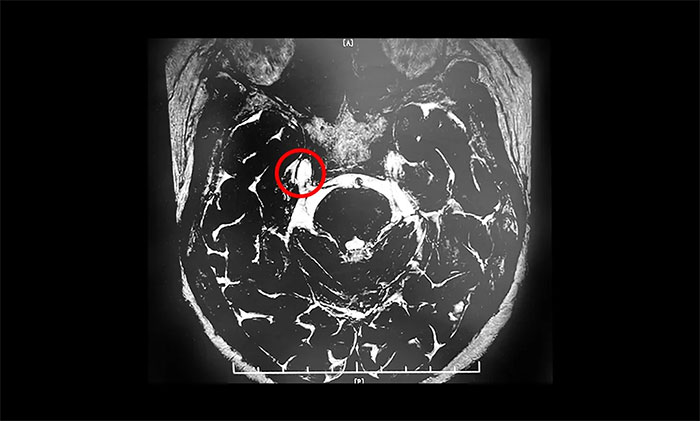

微血管減壓術(shù)是現(xiàn)代神經(jīng)外科典型的微創(chuàng)手術(shù)之一,僅通過(guò)患者耳后發(fā)際內(nèi)4-5cm的切口,于顯微鏡下探查三叉神經(jīng)走行區(qū),將所有可能產(chǎn)生壓迫的血管、蛛網(wǎng)膜條索都“松解”開,并將這些血管以Tefflon墊片與神經(jīng)根隔離。一旦責(zé)任血管被隔離,產(chǎn)生刺激的根源就消失了,三叉神經(jīng)核的高興奮性就會(huì)隨之消失,恢復(fù)正常。絕大多數(shù)患者術(shù)后疼痛立即消失,并保留正常的面部感覺和功能,不影響生活質(zhì)量。